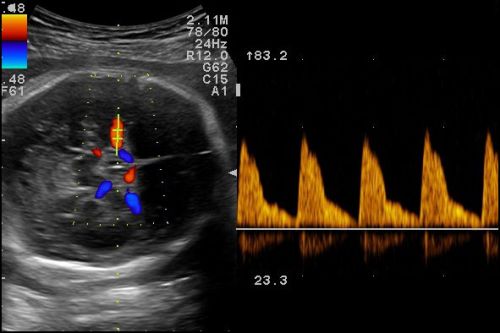

Plazentainsuffizienz, fetale Retardierung,, gefäßrelevante mütterliche Erkrankungen, venöser Doppler (Grundlagen), fetale Anomalien, biophysikalisches Profil, anwendungsbezogene Ultraschallthemen, ausreichend Zeit für Diskussionen, praktische Übungen, Fallbeispiele aus der Praxis, Kasuistiken u.a.